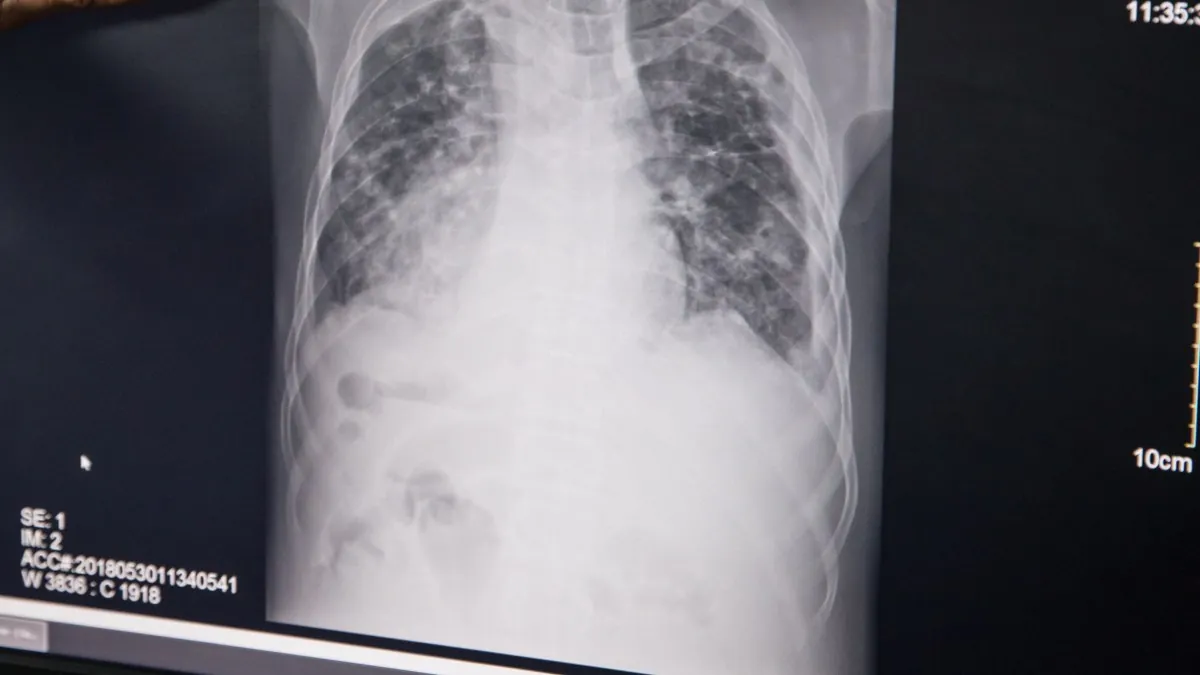

Una radiografía de un paciente con tuberculosis. | Sally Hayden (Europa Press)